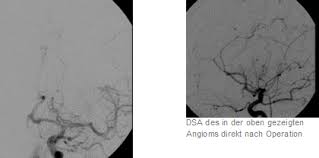

Verschluss Von Angiomen Neuroradiologische Therapie Klinik Fur Radiologie Prof Spreer